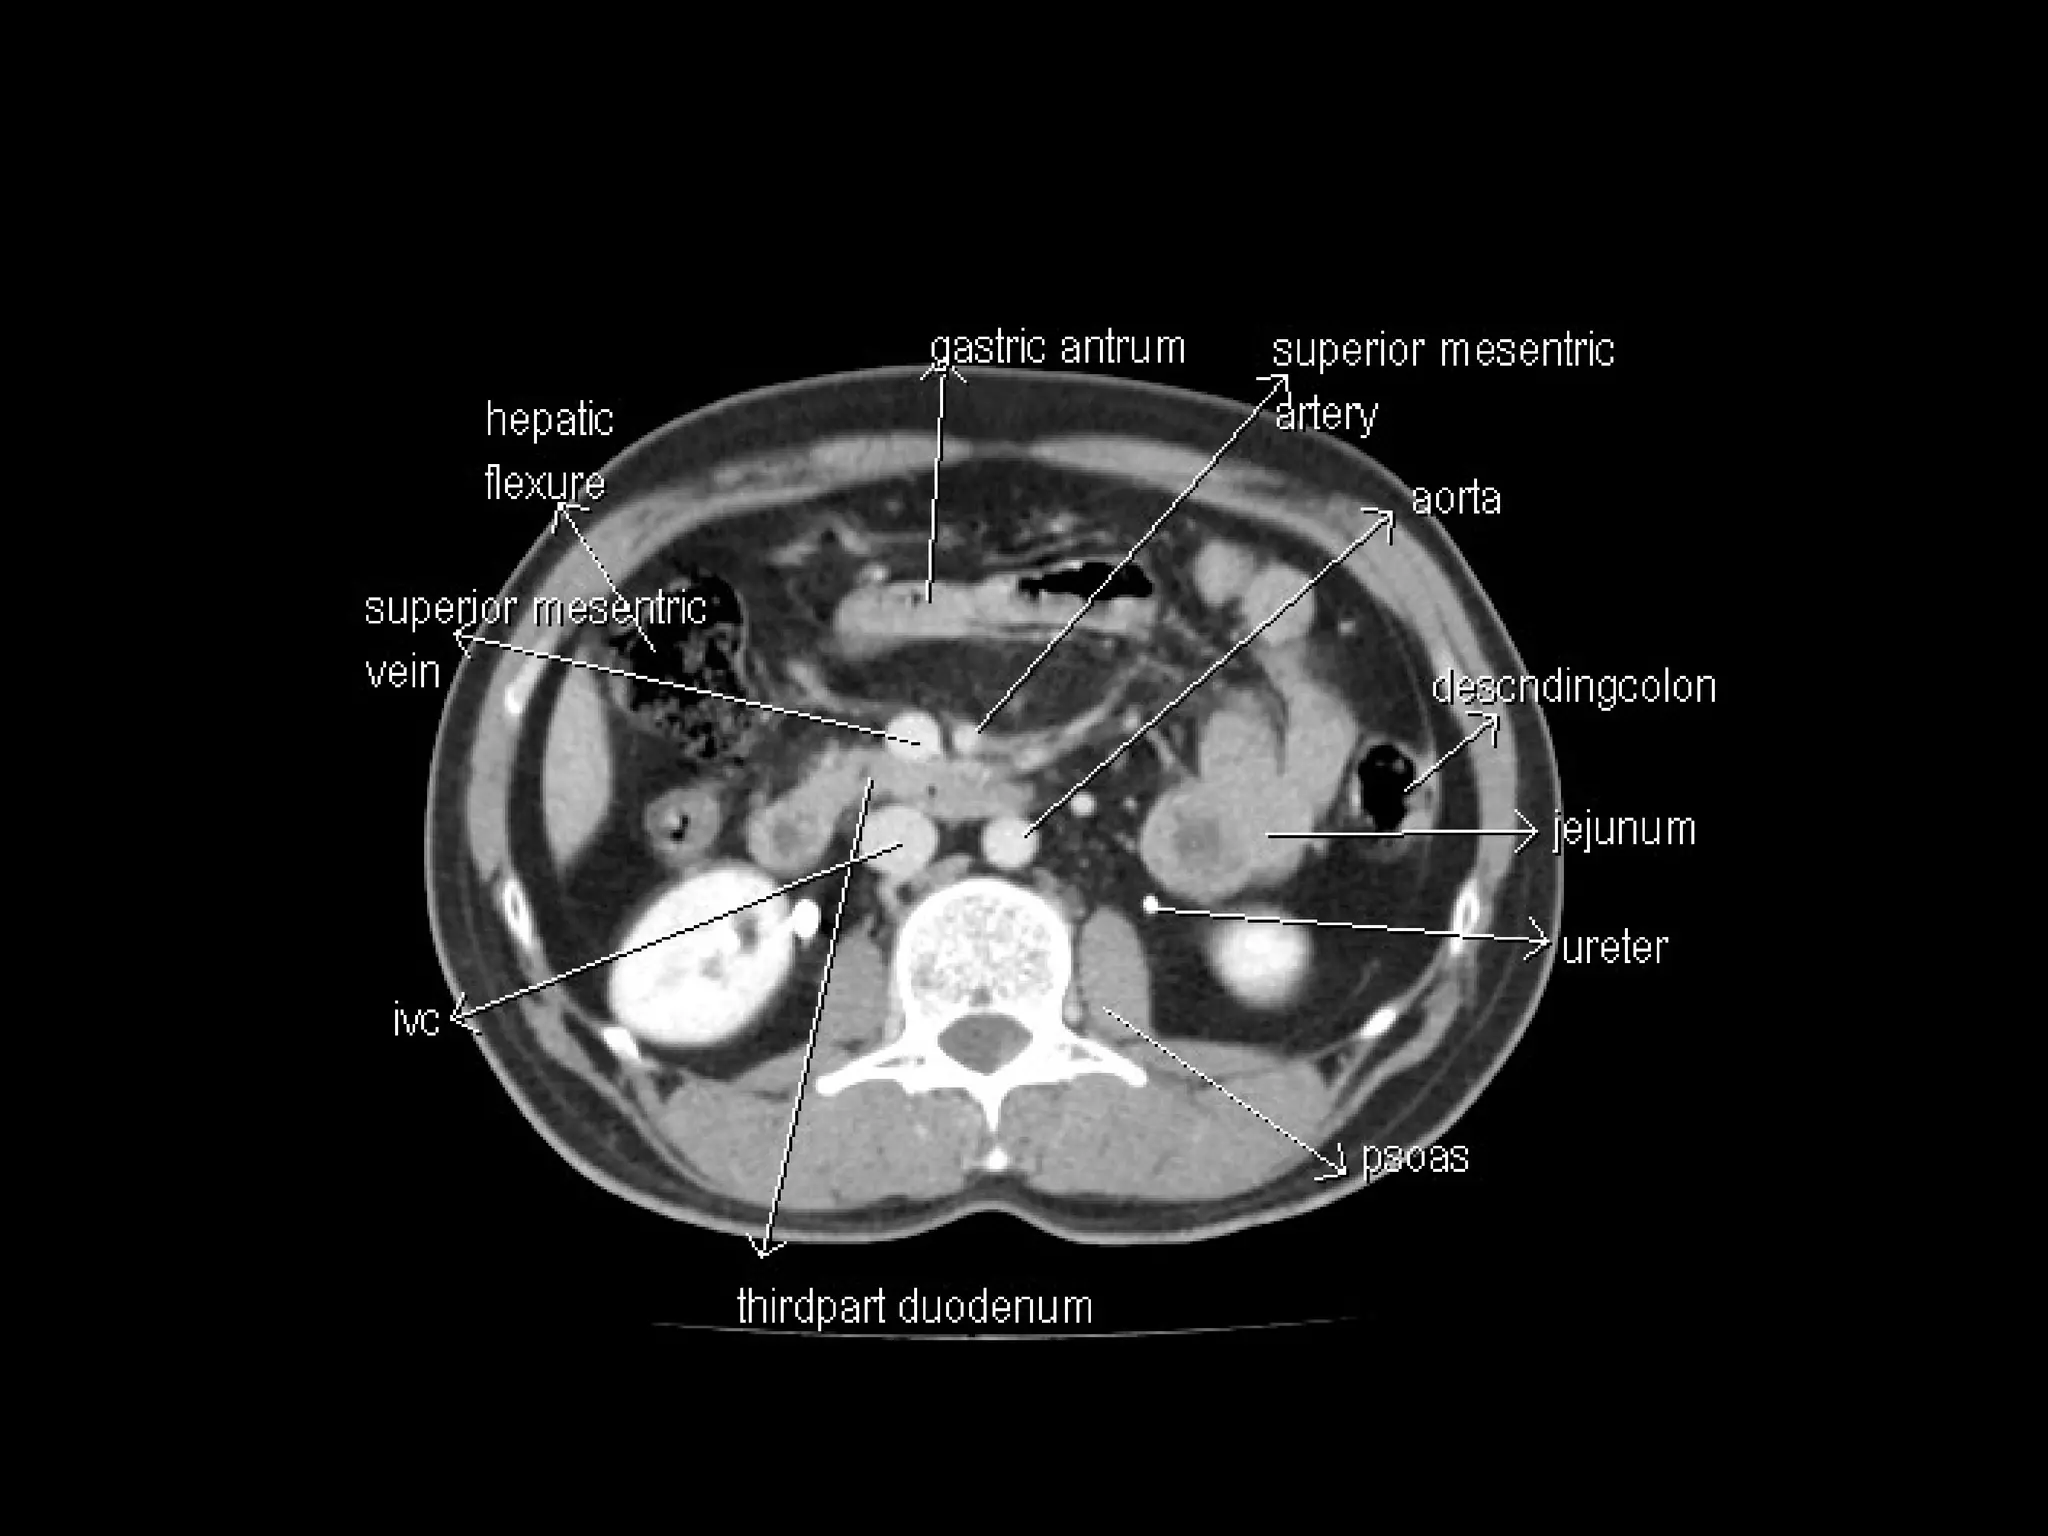

Radiographers are medical professionals who perform diagnostic imaging examinations and procedures to help physicians diagnose and treat diseases. They work under the supervision of radiologists to operate X-ray, CT, MRI, ultrasound and other medical imaging equipment and must have a strong understanding of human anatomy and pathology. Radiographers are responsible for correctly positioning patients, ensuring proper imaging techniques are used, and evaluating the quality of the resulting images.